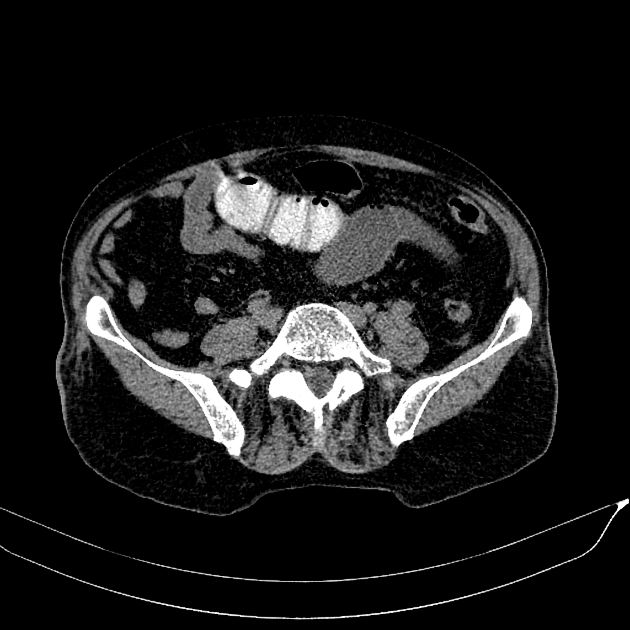

Bezoars

Bezoars - Ảnh 2

» Thông tin: Nam giới – 80 tuổi.

» Lâm sàng: Đau bụng / Nôn.

# Tắc ruột non do bã thức ăn.